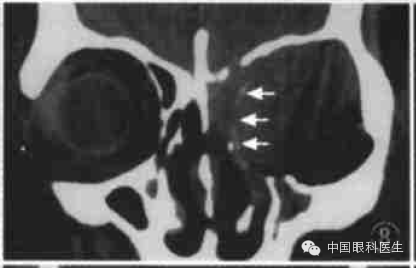

恶性肿瘤呈浸润性增长,CT扫描常显示肿瘤边界不清楚,形状不规则,常合并骨破坏,如副鼻窦癌眶内侵犯(图8)。但有些眶内恶性肿瘤显示类似良性肿瘤的CT征,如形状类圆形、边界清楚、内密度均质、无明显骨破坏等,如横纹肌肉瘤、淋巴瘤、泪腺腺样囊性癌等。

图8 左筛窦恶性肿瘤内侵犯冠状CT显示左筛窦密度增高,筛骨纸板破坏(箭头),眶内侧较大高密度占位病变,形状不规则,眶腔扩大